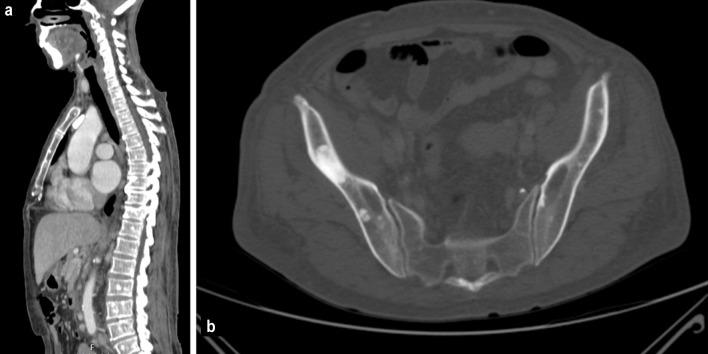

Castleman disease is a rare lymphoproliferative disorder. Co-presentation with polyneuropathy, organomegaly, endocrinopathy, monoclonal protein, and skin changes (POEMS syndrome) has been documented in 11-30% of Castleman disease cases. POEMS syndrome is a rare paraneoplastic disorder characterized by polyneuropathy, organomegaly, endocrinopathy, monoclonal protein, and skin changes. Not all features are required to make the diagnosis. We report a case of a woman who presented with a 1-year history of a left-side supraclavicular swelling associated with constitutional symptoms and symmetrical paresthesia of the lower limbs. In addition, she had skin hyperpigmentation, multiple supra and infra-diaphragmatic lymphadenopathies, hepatosplenomegaly and osteosclerotic lesions. Serum immunofixation was positive for immunoglobulin G-kappa gammopathy. A lymph node excisional biopsy was compatible with Castleman disease. The diagnosis of POEMS syndrome associated with Castleman disease was made. Our patient started treatment with a combination of bortezomib, cyclophosphamide, and dexamethasone with clinical and analytical improvement. Current treatment of POEMS syndrome associated with Castleman disease is focused on the management of POEMS syndrome. Early diagnosis requires a high index of suspicion and is crucial to reduce morbidity and mortality. This case report aims to raise awareness about this rare entity.

卡斯特曼病是一种罕见的淋巴增生性疾病。11%至30%的卡斯特曼病病例有与多发性神经病、器官肿大、内分泌病、单克隆蛋白和皮肤改变(POEMS综合征)同时出现的情况。POEMS综合征是一种罕见的副肿瘤性疾病,其特征为多发性神经病、器官肿大、内分泌病、单克隆蛋白和皮肤改变。并非所有特征都是诊断所必需的。我们报告一例女性患者,她有1年左侧锁骨上肿胀病史,伴有全身症状和双下肢对称性感觉异常。此外,她有皮肤色素沉着、多个膈上和膈下淋巴结病、肝脾肿大和骨硬化性病变。血清免疫固定电泳显示免疫球蛋白G-κ型丙种球蛋白病阳性。淋巴结切除活检结果符合卡斯特曼病。诊断为与卡斯特曼病相关的POEMS综合征。我们的患者开始接受硼替佐米、环磷酰胺和地塞米松联合治疗,临床和分析指标均有改善。目前,与卡斯特曼病相关的POEMS综合征的治疗重点在于POEMS综合征的管理。早期诊断需要高度的怀疑指数,对于降低发病率和死亡率至关重要。本病例报告旨在提高对这种罕见疾病的认识。